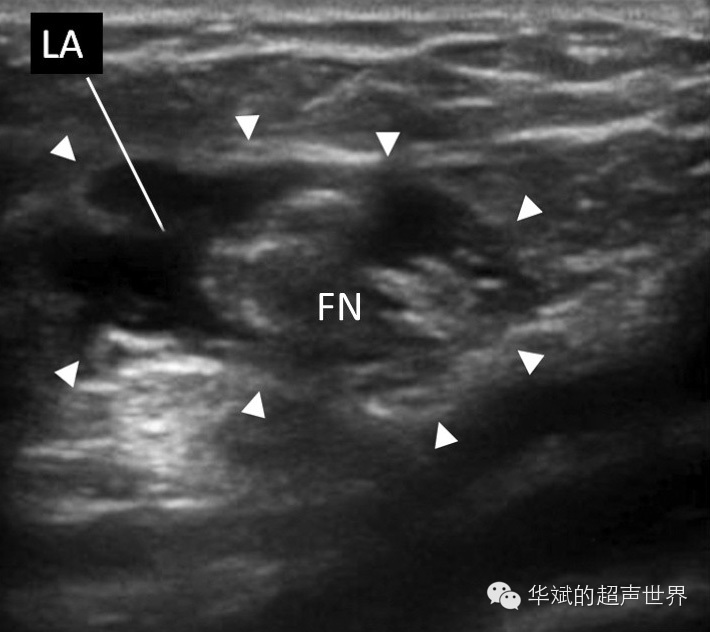

避免将针尖刺入神经束内,一般首先将针尖置于神经后方,注射一半药物后再退针,然后尖针尖至于神经前方注射另一半药物。使注射的药物包绕在神经周围为佳(图9)。

9 股神经阻滞后,显示局麻药包绕在神经周围。LA:局麻药,FN:股神经。三角箭头所示范围为局麻药的分布情况